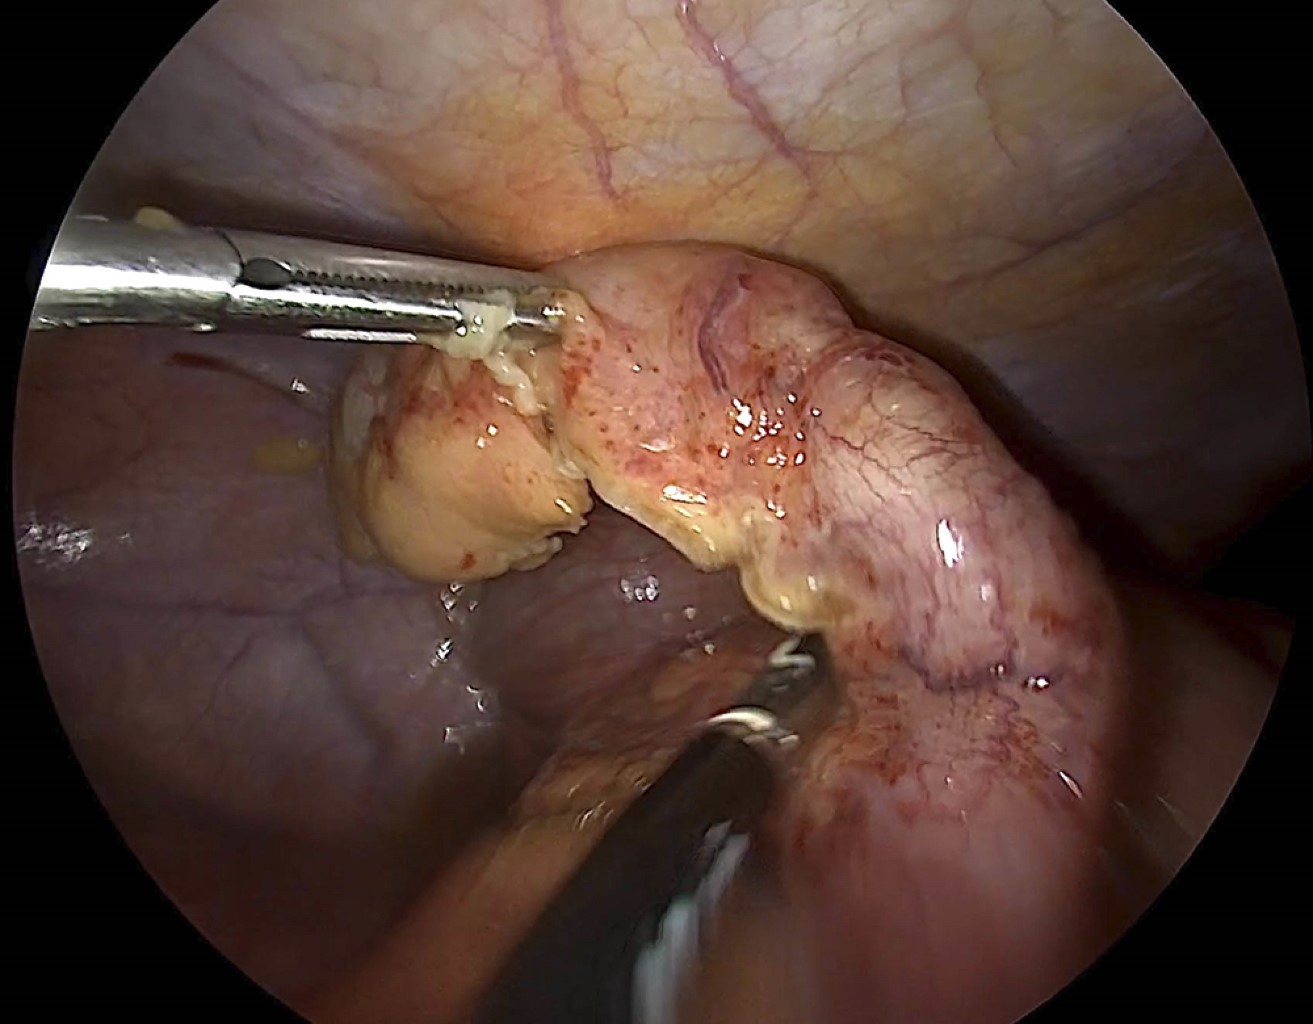

Hombre de 19 años que niega antecedentes quirúrgicos, así como crónicos degenerativos. Al interrogatorio de antecedentes familiares de cáncer, todos fueron negados. Se presentó al servicio de urgencias con dolor abdominal de tipo cólico, de inicio periumbilical irradiado a fosa ilíaca derecha, acompañado de náuseas, vómito de contenido gastroalimentario en tres ocasiones e intolerancia a la vía oral, a la exploración física contó con datos de irritación peritoneal. Se realizaron estudios de laboratorio con leucocitos de 10.97 × 109/L y neutrófilos de 85%. Se realizó tomografía de abdomen donde se reportó ileítis terminal con ganglios mesentéricos de aspecto reactivo, apéndice cecal con diámetro limítrofe de 6 mm sin visualizar la punta (Figura 1). Al presentar cuadro de abdomen agudo con alta sospecha de apendicitis aguda se efectuó laparoscopía diagnóstica y apendicectomía (Figura 2); los hallazgos de importancia de dicho procedimiento fueron: apendicitis aguda, abscedada, con un absceso de hueco pélvico de 15 cm3, se decidió manejo del muñón apendicular con ligadura simple e invaginación con punto en Z, reportando un sangrado de 10 cm3. Se envió a patología pieza quirúrgica y dos semanas después se entregó reporte con diagnóstico de tumor neuroendócrino bien diferenciado grado 1, según clasificación de la OMS (Figura 3), con las características comentadas en la Tabla 1.

Figura 2